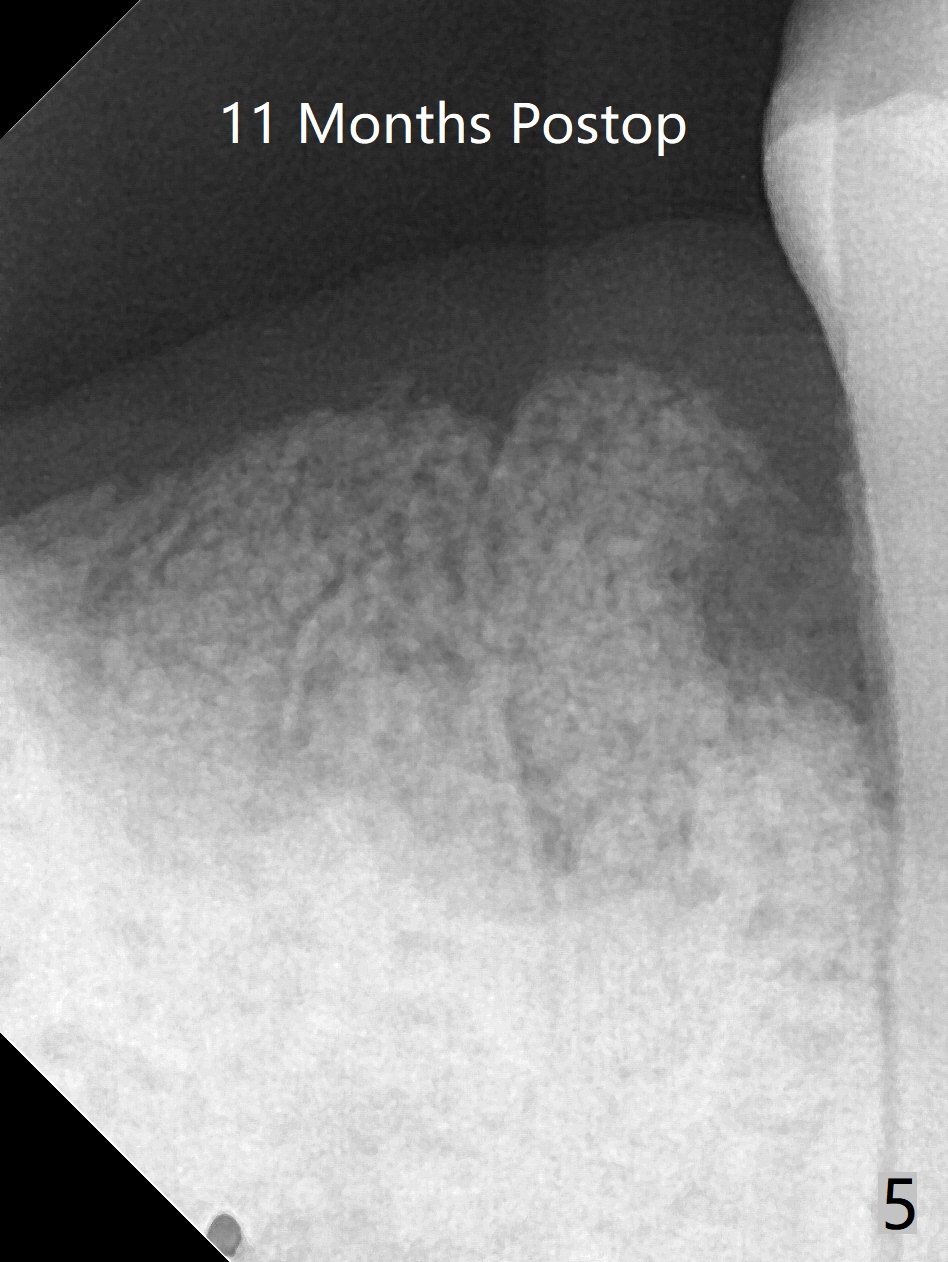

A 52-year-old man with poor dentition has concept of socket preservation when he wants extraction at #30. There is bone loss with the presence of the septum (Fig.1,2 *). Mixture of Vanilla graft and Osteogen is packed around the septum (Fig.3). With blood supply from the septum, the allograft should be more efficiently converted to the native bone than without the septum. The socket is closed with Osteogen plug and suture (Fig.4). In fact the bone height increases by 2.4 mm over the septum 11 months postop (Fig.5,6). In contrast there is apparently no bone regeneration in the socket of #28 four months postop without bone graft (Fig.7). Implant to be placed in the "empty" socket may fail. With bone graft, the ridge at #30 is higher than the surrounding bone 18 months postop (Fig.8 ^) with formation of the cortex on the top of the alveolus <). The average bone density is 1500 units. In contrast, without bone graft, the buccal plate at #28 is missing 11 months postop (Fig.9 >) with average bone density at 500 units. The implant at #28 should be long to engage to the apical native bone (Fig.10) with incision in case of need for bone graft. Sticky bone will be placed mesial to #29.